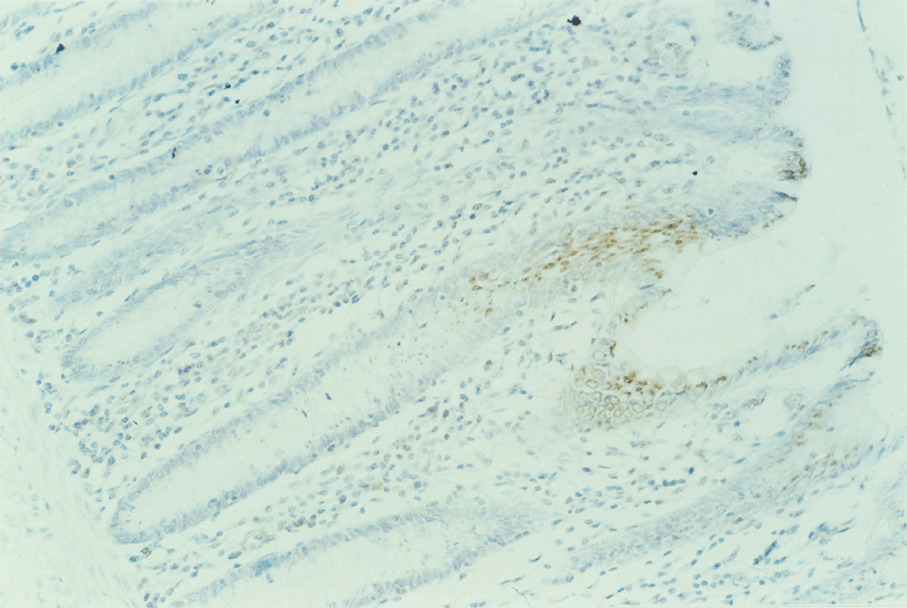

8:6. Photomicrograph of polyposis coli mucosa stained for p62c-myc protein.

8:7. Photomicrograph of polyposis coli mucosa stained for p62c-myc protein.